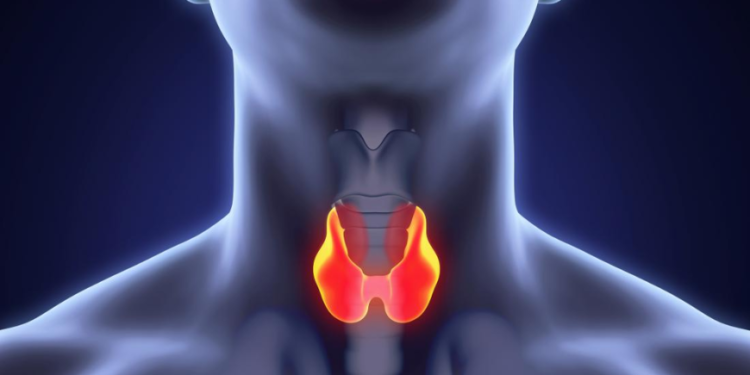

थाइराइड ग्रन्थि घाँटीको अगाडि पुतली आकारको सानो ग्रन्थि हो। यसले शरीरको मेटाबोलिजम, मुटुको धड्कन र तापक्रम नियन्त्रण गर्छ। यदि थाइराइडमा गाँठो वा अन्य समस्या देखियो भने समयमै उपचार नगर्दा स्वास्थ्यमा जटिलता आउन सक्छ।